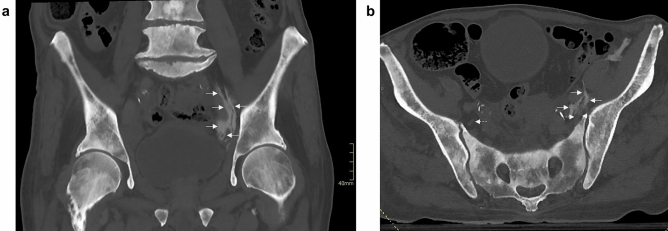

Figure 2.

Coronal (a) and axial (b) CT imagery of the S-FICB case wherein the contrast mixture reached the ON (left side). The injectate was found to involve the ON in the retroperitoneal compartment at the level of the first sacral vertebra, which was also the maximum height that was reached. Dashed arrows point to the ON, while solid arrows point to contrast.